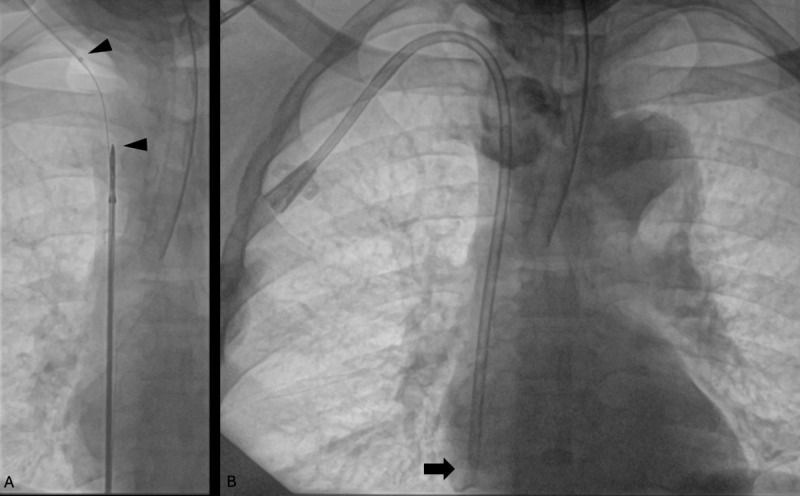

本病例描述了Merit Medical在闭塞的下腔静脉中使用Surfacer®Inside-Out Access Catheter System (SIO)。该手术通常采用右股静脉入路,有急性髂腔血栓形成的禁忌症,因为可能发生栓塞。在病史和影像学检查后,确定该病例的闭塞是慢性的,并决定使用留置导管进行SIO手术。本病例展示了SIO手术在已用尽所有其他选择的中心静脉闭塞患者的某些情况下的应用。

This case describes the use of the Surfacer® Inside-Out Access Catheter System (SIO) from Merit Medical in an occluded inferior vena cava. The procedure typically utilizes right femoral vein access with contraindications of acute iliocaval thrombosis due to possible embolization. After history and imaging studies, the occlusion was determined to be chronic in this case, and a decision was made to employ the SIO procedure using an indwelling catheter. This case demonstrates the use of the SIO procedure in certain settings in patients with central venous occlusions who have exhausted all other options.